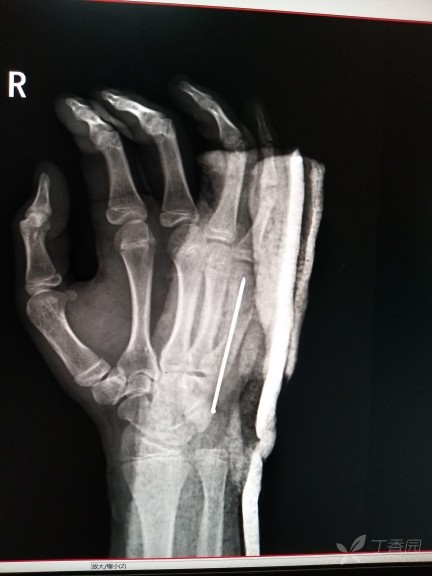

由于暴力拳击所致 第五掌骨骨折 4天前手术后为什么无名指也有些疼 很难弯曲全 按片子我多久可以不用第五掌骨骨折需要多久